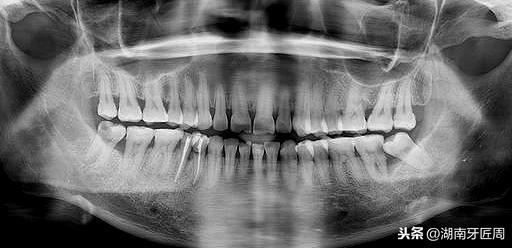

图片2.右侧智齿倾斜阻生顶坏前牙

图片3

图片4.右侧智齿水平阻生,你能知道我的存在?

图片5.左侧智齿埋伏水平阻生